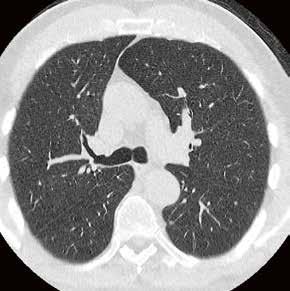

Thorax-CT im Rahmen einer Lungenkrebsfrüherkennungsstudie. Die Voruntersuchung lag als externe kontrastmittelgestützte Thorax-CT vor. Bei der dosisoptimierten Low-Dose-CT liegt die Strahlenexposition nur noch im Bereich von zwei konventionellen Röntgenaufnahmen des Thorax, die Bildqualität ist für die Fragestellung nach Herdbefunden aber dennoch eindeutig ausreichend, selbst interstitielle Lungenveränderungen lassen sich hier noch beurteilen.

Prof. Dr. med. Johannes Weßling Zentrum für Radiologie, Neuroradiologie und Nuklearmedizin Abb. 3 a: kontrastmittelgestützte Thorax-CT, externe Untersuchung; DLP 216,0 mGy × cm / 3,9 mSv. Abb. 3 b: dosisoptimierte Low-Dose-Thorax-CT, Canon Aquilion Prime SP, Rekonstruktion: AiCE; DLP 13,9 mGy × cm / 0,25 mSv.